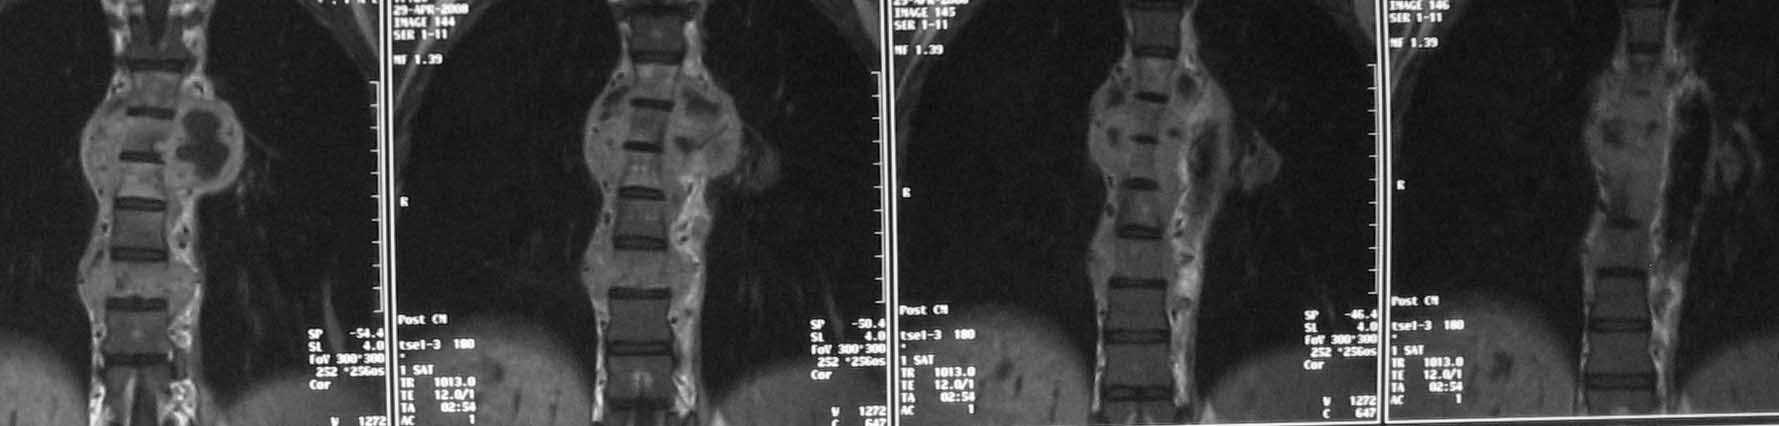

Дополнительное изображение 2. Наиболее поражены 5,6,7 и 9 грудные позвонки.

Литические изменения в структуре тел позвонков особенно в нижнегрудном отделе при сохраненном дисковом пространстве наводит на мысль о спондилите с вторичным вовлечением дискового пространства( его исчезновение на уровне

5-6-7 позвонков).